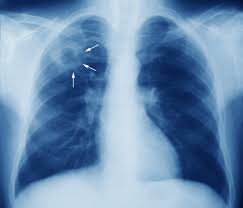

Туберкулез Легких Фото

Туберкулез Легких Фото 84 фото